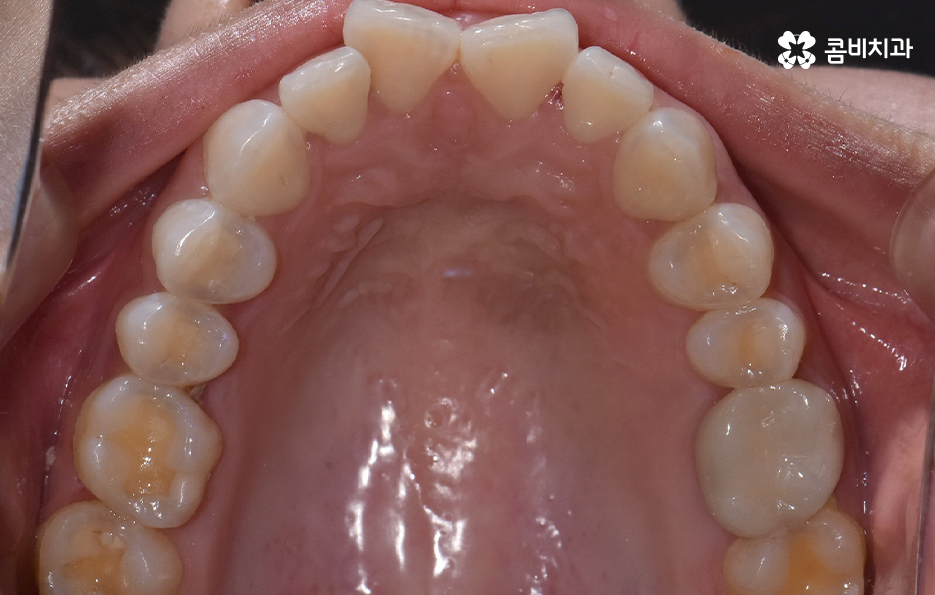

앞니가 틀어지는 원인부터 살펴보면 대표적인 원인은 치열 공간의 부족으로 치아는 제자리에 가지런히 놓이기 위해 충분한 공간이 필요한데, 치아 크기는 정상인데 턱뼈가 작거나, 젖니가 너무 일찍 빠져 앞니가 원하는 방향으로 자리 잡지 못하면 틀어짐이 쉽게 나타날 수 있어요

특히 앞니는 치열에서 먼저 눈에 띄는 자리라 공간이 조금만 부족해도 서로 밀리며 비틀리거나, 한쪽으로 회전하는 형태로 틀어지는데 어린 시절 안좋은 습관이나 편작 습관이 있던 사람들도 턱뼈 성장 불균형이 나타나 치열 공간이 부족해지는 일이 나타날 수 있었어요

그리고 혀는 생각보다 강한 근육이라 치아 배열에 큰 영향을 줄 수 있는데 정상적인 혀 위치는 윗니 뒤쪽, 즉 구개에 가볍게 붙어 있는 상태지만 혀가 아래쪽에 위치하거나 앞쪽으로 밀려 나오는 습관이 있으면 앞니는 점점 밖으로 밀리게 되고 특히 수면 중 입을 벌리고 자는 사람, 말할 때 혀가 치아를 밀어내는 사람은 앞니 틀어짐이 나이가 들면서 더 심해지는 경우가 많이 있었어요

또한 나이가 들면서 앞니 주변 잇몸이 내려가고 뼈가 약해지면 치아를 잡아주는 힘이 줄어드는데 이때 앞니는 미세한 힘에도 쉽게 움직이기 시작해서 나이 들었더니 앞니가 벌어지기 시작했다라고 호소하는 경우가 많은데 이는 구조적 지지력이 떨어져 생기는 변화로 볼 수 있어요

이처럼 앞니 틀어짐은 다양한 원인에 의해 나타날 수 있는데 앞니 틀어짐이 경미한 수준일 때 어떤 교정 방법이 효과적인지 살펴보면 특히 앞니 틀어짐이 심하지 않을 때는 전체 교정보다 부담이 적고 기간도 짧은 경우가 많으며 중요한 건 원인을 정확히 잡고 그에 맞는 치료를 선택하는 것이라 할 수 있었어요

앞니 틀어짐 교정 방법 경미한 수준일 때는 부분 교정 방식은 치료 기간이나 방법 면에서 비교적 간단한 치료가 가능한데 앞니 6개 정도에만 브라켓을 부착해 미세한 틀어짐을 바로잡는 방식으로 치아가 크게 회전하지 않았거나 공간이 약간 부족한 정도라면 효과적이며 기간도 보통 3~6개월로 짧은 편으로 이 방식은 앞니 배열을 빠르게 정리하면서도 자연스러운 라인을 만들 수 있어요.

부분교정과 투명교정 방식은 대표적으로 앞니 틀어짐이 경미한 수준일 때 적용하기 적합한 방식이지만 교합의 개선과 얼굴형의 변화를 목표로 해야하는 경우라면 환자 분들이 앞니만 고치는 것을 원한다고 해도 전체교정이 필요한 케이스도 많기 때문에 우선적으로 정밀검진을 통해서 나에게 적합한 치료 계획을 세우는 것이 중요하겠고 치아교정의 목적에는 치료 후의 지속성, 안정성 또한 함께 고려해야 한다는 점에서 앞니 틀어짐의 원인을 개선하여 재발을 방지하는 것까지도 잘 고려하실 필요가 있었어요

결론적으로 앞니가 틀어지는 이유는 생활습관, 구조적 문제, 뼈의 변화, 혀의 위치, 교합 등 다양하게 얽혀 있으며 특히 틀어짐이 경미할 때, 혹은 앞니의 변형이 시작되는 초기에는 비교적 간단한 교정 방법으로도 충분히 개선할 수 있고, 비교적 치료 기간도 짧아 부담이 적지만 중요한 것은 원인을 함께 해결해야 재발을 막을 수 있다는 점으로 무엇보다 나에게 적합한 치료 계획을 경험 많은 교정 전문의와 충분히 상의하여 판단하시길 바라고 있어요